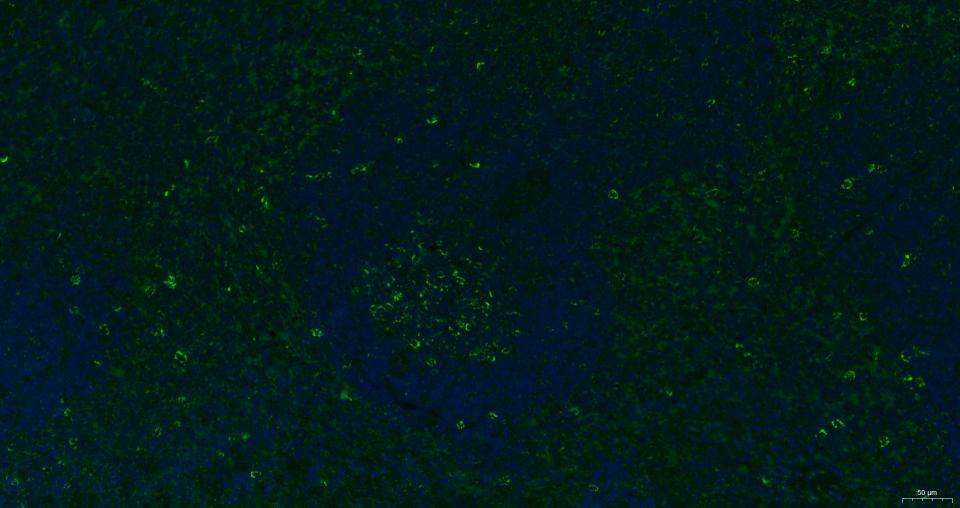

| IF | Human, Mouse, Rat | 1:100-500 |